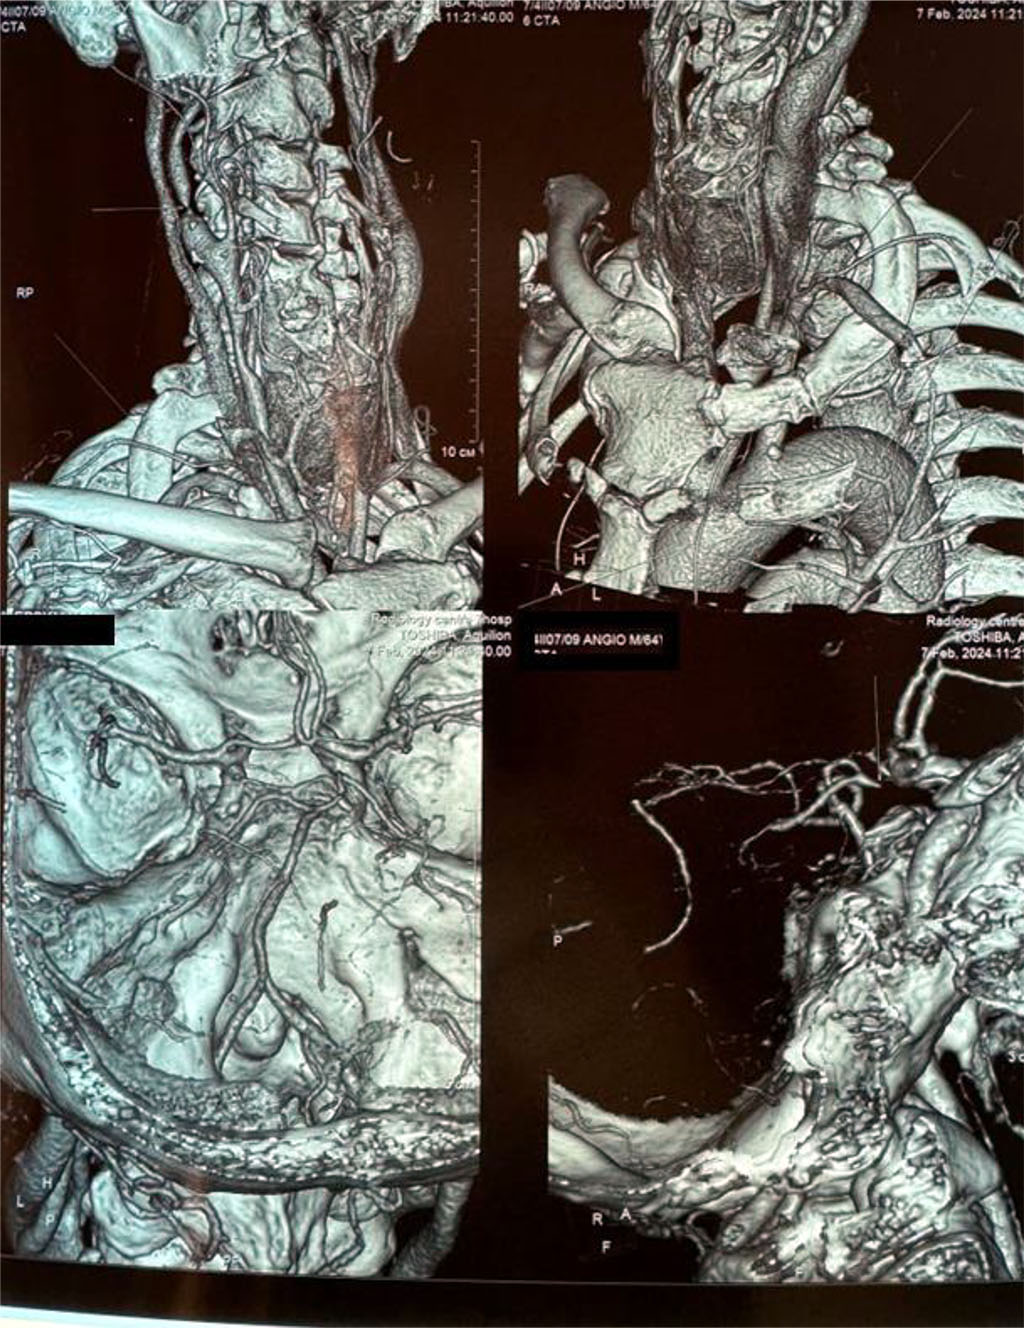

CT angiography revealed that the right external carotid artery is stenotic up to 85%, the internal one is up to 90%, and the circle of Willis is closed despite this. Fig. 2.

Figure 2. CT angiography (3D reconstruction) in a patient with 85% stenosis of the right external carotid artery and 90% of the internal carotid artery